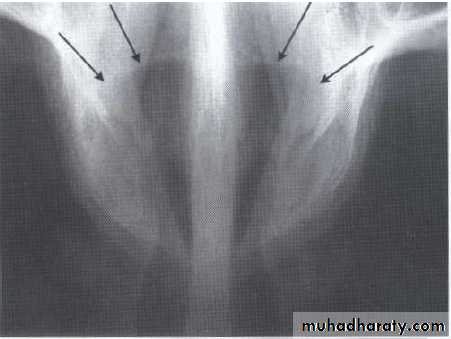

Lesions in midline of maxilla

Nasoalveolar cyst (nasolabial cyst)Located in the vestibule of upper lateral & cuspid area , its soft tissue lesion may not produce any radiolucency ,in such case aspiration &/or radiograph with radiopaque contrast media is used to establish the diagnosis. Teeth are vital , clinically involve the lip & the floor of the nose .

The radiograph shows erosion of the alveolar bone (o) and elevation

of the floor of the nasal fossa (arrows).• Globulomaxillary Cyst

• It is located between the maxillary central incisors (which are vital). This lesion dose not exist as an entity but it represents an incisive canal cyst.• Nasopalatine Cyst

Also called nasopalatine canal cyst, incisive canal cyst, median palatine cyst , or median anterior maxillary cyst.*It is located in the midline between the upper central incisors. Note the superimposed shadow of nasal

spine causing the cyst to appear heart shaped.

The teeth are vital.

This cyst causes the roots of the central incisors to

diverge, and occasionally root resorption occur.

*Treatment by excision.